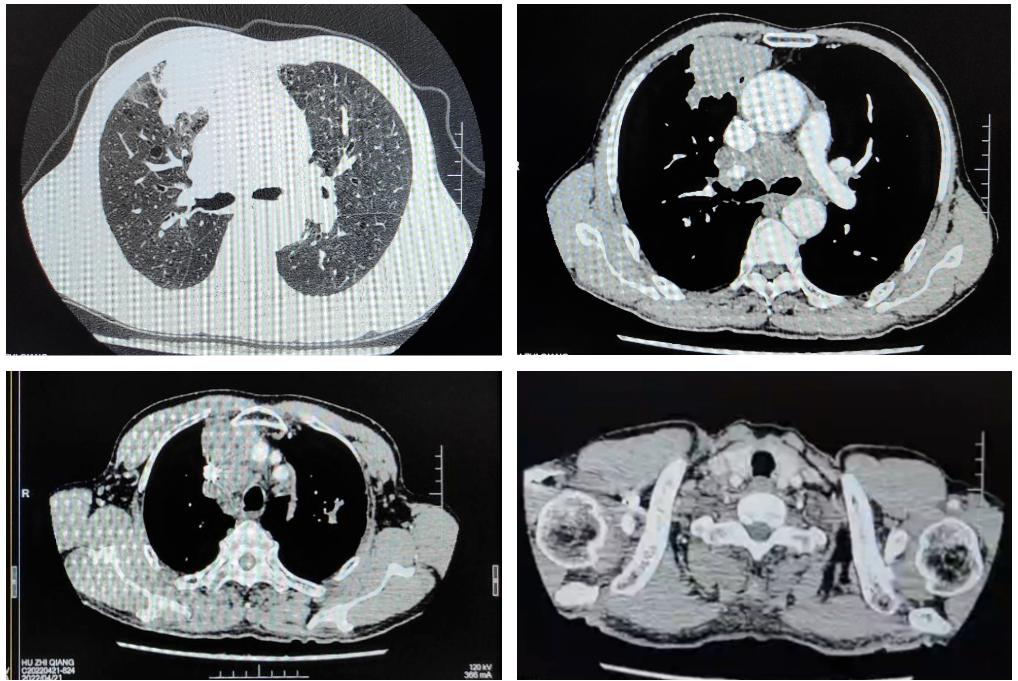

2022年4月21日CT:1.右肺上叶前段周围型肺癌(71mm×36mm)伴纵隔多发淋巴结肿大。2.双上肺、左下肺结核可能性大,CT表现为稳定性征象。3.慢性支气管疾患:肺气肿;肺大泡。4.肝多发小囊肿;肝内钙化灶。

2022年4月22日支气管镜检查:1.左上叶病变:Ca?其他 2.纵隔肺门淋巴结增大(EBUS探及)。病检:涂片、5/4R、7组淋巴结EBUS-TBNA;6/左上叶。

原发性支气管肺癌 右上肺小细胞肺癌 T4N3M1b 脑转移 IVa期(广泛期)。